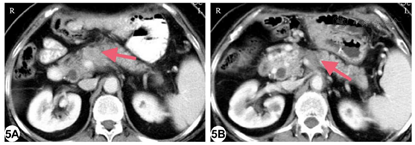

术后第11天患者并发胰瘘,引流管中持续引出胰液,颜色尚清,最大量接近500 ml/d。后出现引流不通畅情况,给予患者经皮经肝穿刺置管引流、禁食禁水、胃肠外营养等治疗。患者恢复顺利,于术后第44天带管出院。1个月随访增强CT肿瘤完全灭活。手术后约8个月随访增强CT显示胰体局部肿瘤复发以及脾静脉受累(图5A)。患者一般情况良好,无肿瘤远处转移。患者于11月17日再次接受开腹RFA,在IOUS引导下将射频电极精确置入肿瘤,手动射频条件与先前相同,进行两点次消融(分别为8、6min)。术后患者再次出现胰瘘,引流通畅,随后并发腹腔出血,通过介入栓塞治疗后停止。腹腔引流逐渐减少,拔除引流管后无不适,患者出院。患者在术后8年状况良好,无肿瘤复发迹象(图5B)。